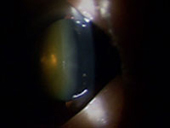

| 白内障軽度 | 白内障軽度(皮質白内障) | 白内障進行例 |

白内障術後 眼内レンズ挿入眼